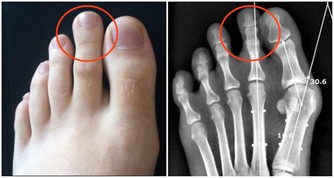

空鼻症到底是什麼?即過分的鼻甲切除性手術導致的鼻腔黏膜萎縮及一系列伴發症狀。

天津醫科大學第二醫院耳鼻喉科主任醫師黃永望曾說:

“患者一般是之前患有慢性鼻炎、鼻息肉、鼻竇炎等鼻部病症,想通過手術通暢鼻腔,

但手術後感覺還是不夠通暢或者過度通暢,部分患者就成了空鼻症。”

用患者的話說是:“感覺被世界遺棄”、“我寧可斷只胳膊或斷條腿”、“每次呼吸都像被刀子扎一樣”……

另外,除了身體上每天要遭受“生不如死”的痛苦外,半數的空鼻症患者還伴有精神抑鬱症狀。